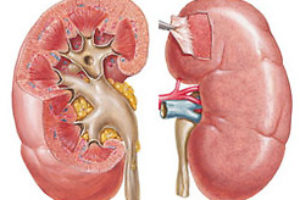

Kidney condition requires close attention, as they often nephrological disease or asymptomatic, or after the acute onset can turn into a chronic form. Get prices Diagnostics The gradual deterioration …